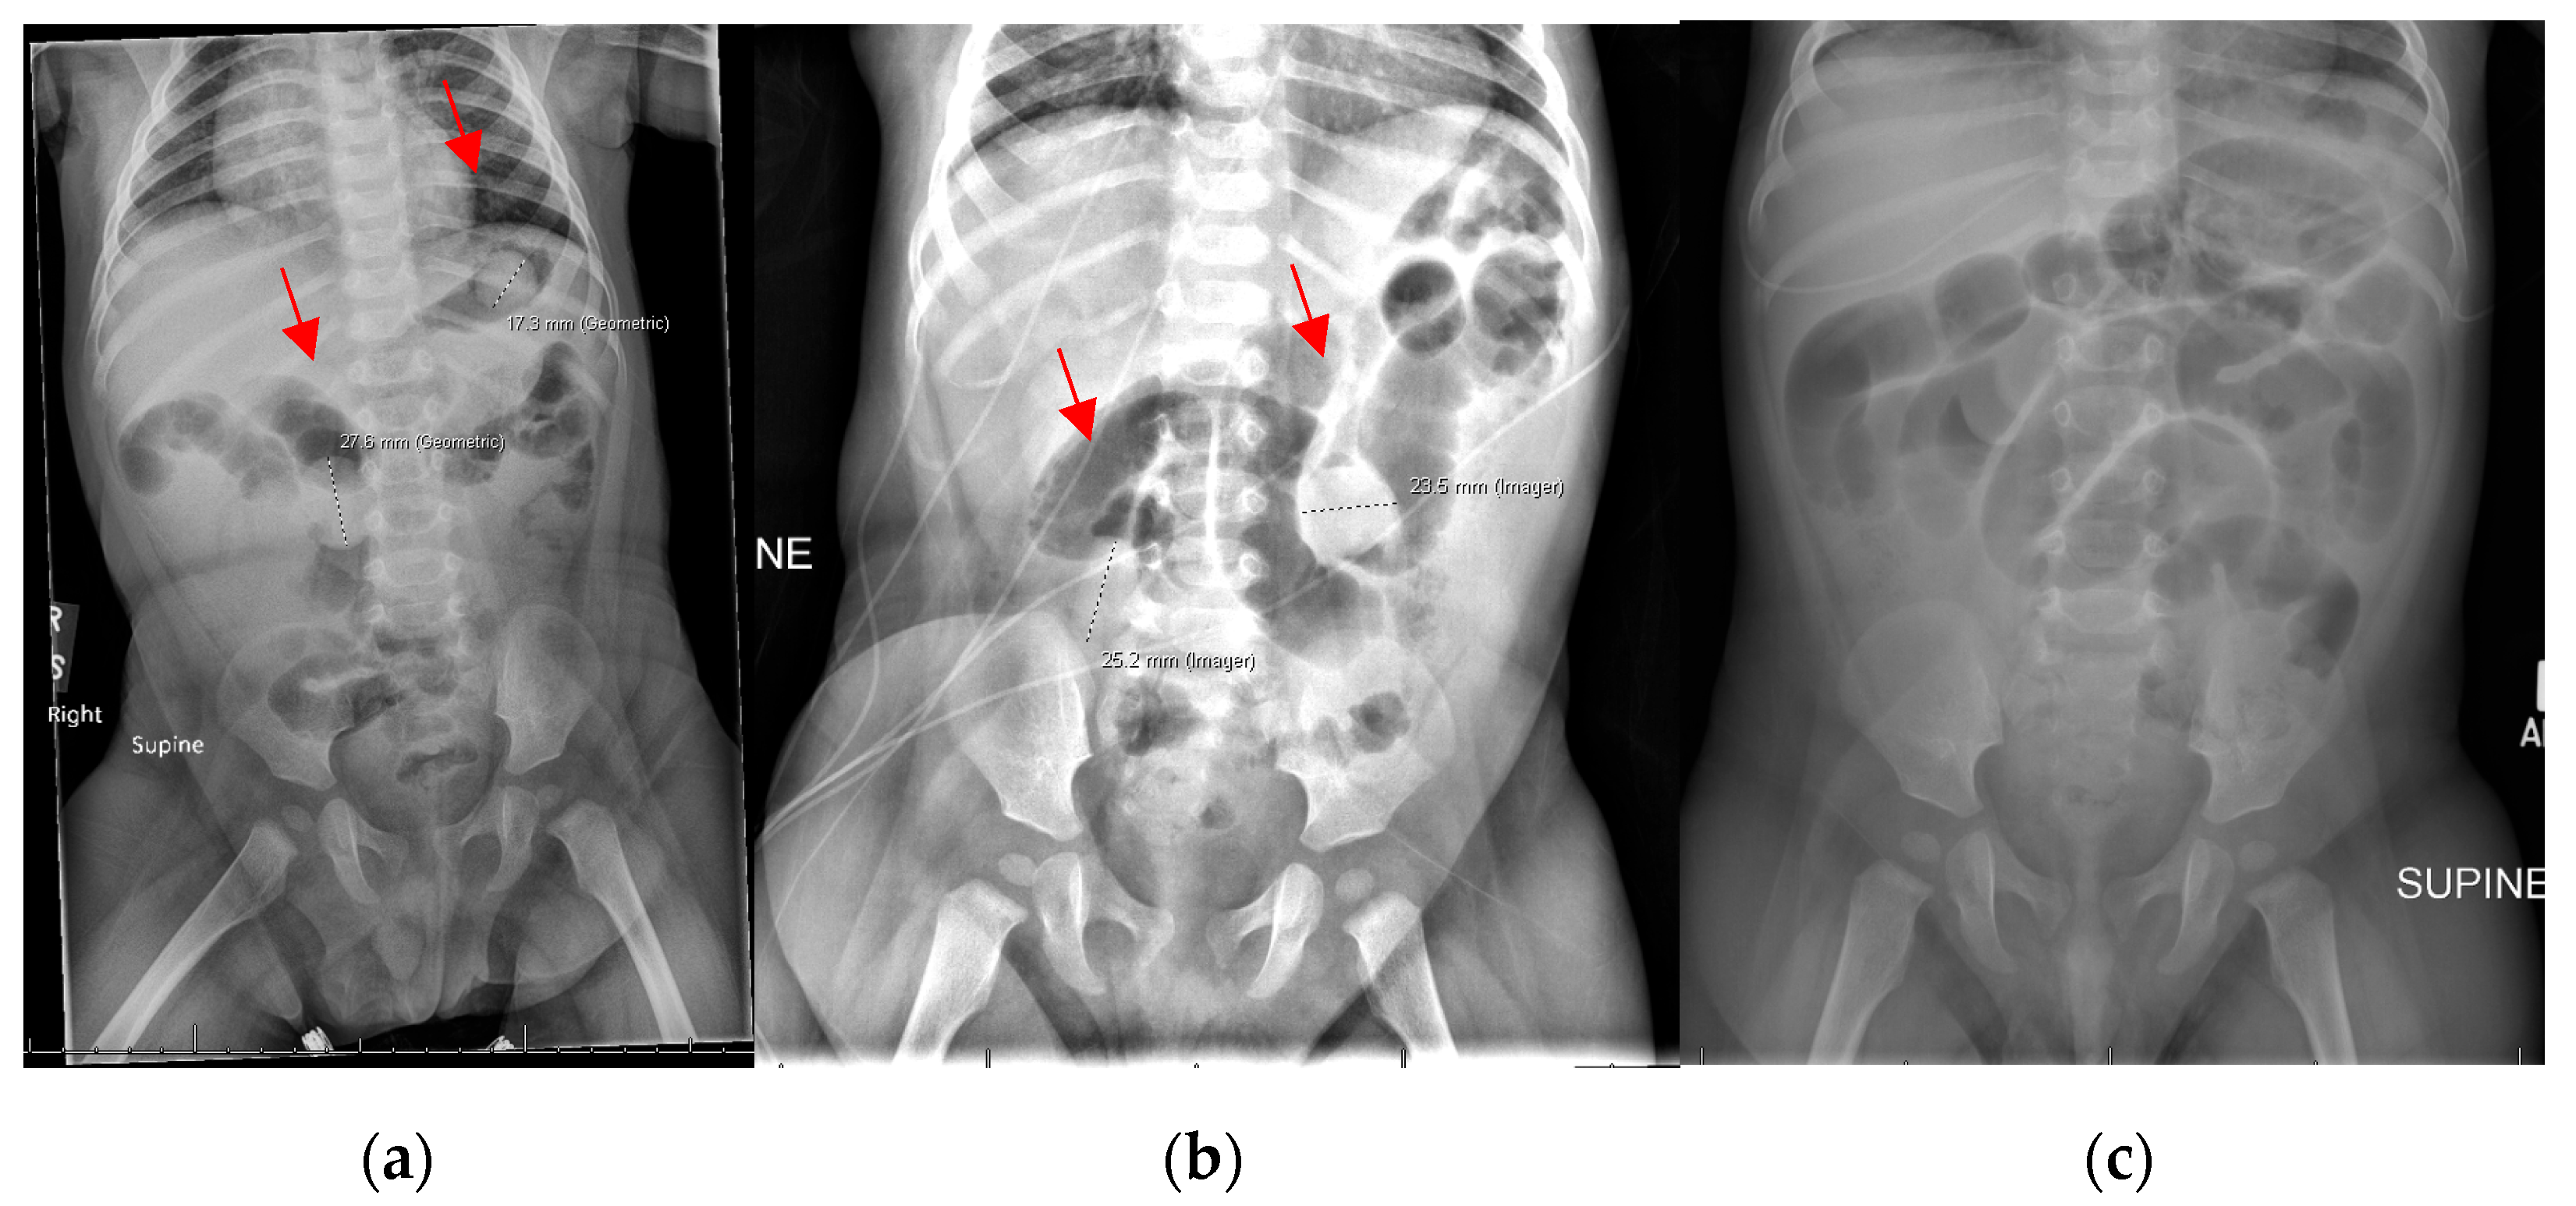

3.1. Patient 1

3.2. Patient 2

3.3. Patient 3